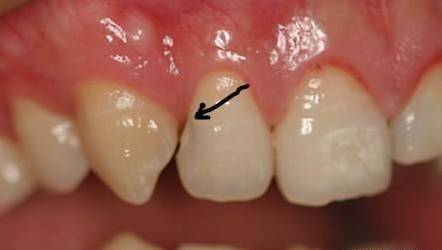

原因二:龋齿(蛀牙)

还有一种可能就是龋坏,即虫牙,也会变黑。这种情况一般去补牙就行了,补牙前都会把龋坏先清理干净,再做充填。早期蛀牙只需要填牙就可以了,到了中后期的蛀牙就需要根管治疗或者拔除了。